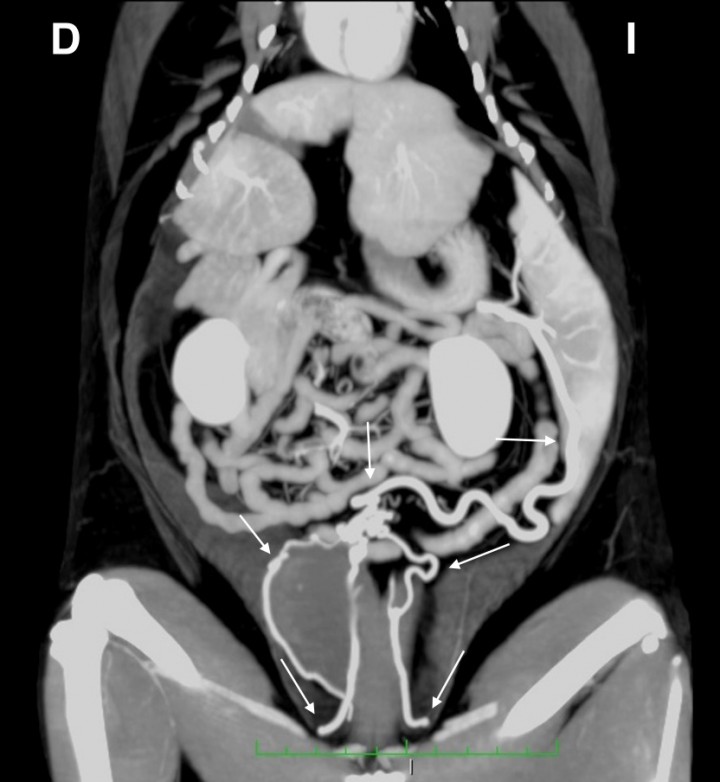

La TC confirmó la presencia de un vaso anómalo de gran calibre con origen en la vena esplénica que se dirigía caudalmente y que, tras un recorrido extremadamente tortuoso, se dividía, craneal a la vejiga de la orina, en tres vasos de menor calibre: dos se dirigían hacia caudal hasta insertarse en la vena ilíaca externa derecha y el tercero lo hacía en la vena ilíaca externa izquierda (Fig. 3). Estos hallazgos fueron consistentes con la presencia de una comunicación portosistémica extrahepática con origen en la vena esplénica e inserción múltiple en las venas ilíacas externas. También se visualizaron a nivel hepático varias lesiones de entre 2,5 y 4 cm aproximadamente, hipoatenuadas y de bordes irregulares. Tras la administración del contraste intravenoso se observó un realce leve y heterogéneo de las mismas y moderadamente inferior al del parénquima hepático (Fig. 4). Los diagnósticos diferenciales para estas lesiones fueron los mismos que los descritos previamente en los hallazgos ecográficos.

<p>Imagen tomográfica dorsal del abdomen tras la administración de contraste intravenoso, en ventana tejido blando y con proyección de máxima intensidad (MIP) con sumatorio de cortes. Se observa el recorrido de la comunicación desde su origen en la vena esplénica hasta su inserción múltiple en las venas ilíacas externas (flechas). D: derecha, I: izquierda.</p>

Figura 3

Imagen tomográfica dorsal del abdomen tras la administración de contraste intravenoso, en ventana tejido blando y con proyección de máxima intensidad (MIP) con sumatorio de cortes. Se observa el recorrido de la comunicación desde su origen en la vena esplénica hasta su inserción múltiple en las venas ilíacas externas (flechas). D: derecha, I: izquierda.